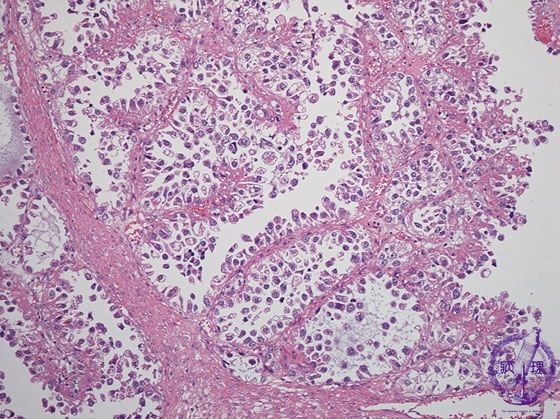

Histology (HE stain, intermediate power): Carcinoma cells with clear cytoplasm proliferated in papillary or tubular structure.